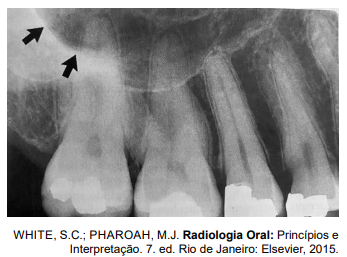

Analise a imagem radiográfica a seguir.

As estruturas anatômicas apontada pelas setas pretas correspondem ao